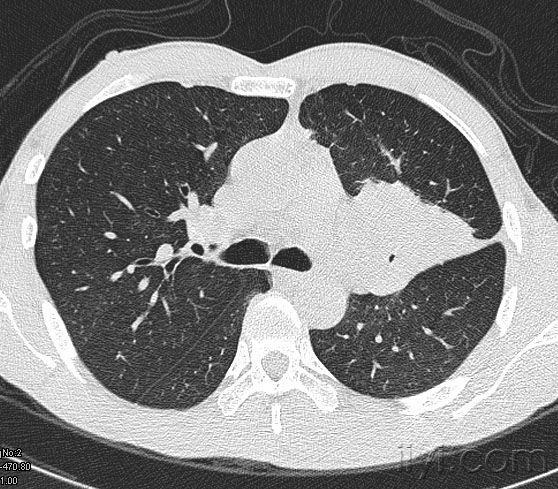

中央型肺癌ct

在ct上,肺癌按照发生部位可以分为以下3种类型: 1,中央型肺癌:指肿瘤

简述中央型肺癌特点及影像表现

中央型肺癌一例直接征象和间接征象都有哪些